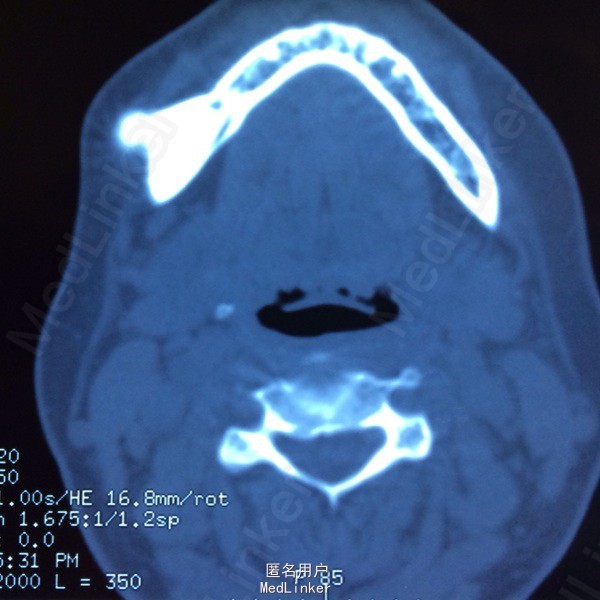

中年女性,慢性病程。患者于十余年前发现右面部包块,质地硬,无疼痛,未有明显增大变小,否认下唇麻木等症状未经治疗,近月来自觉肿块逐渐增大,余无不适,就诊求治。

查体:双侧下颌区不对称,右侧下颌较左侧膨隆,可扪及包块,质地硬,无压痛,无活动度,边界清,口内46、47前庭沟内可扪及,开口度开口型及口内牙体检查未见明显异常。CT示:右下颌骨高密度影,边界清。

诊断:右下颌骨骨瘤 处理:手术治疗